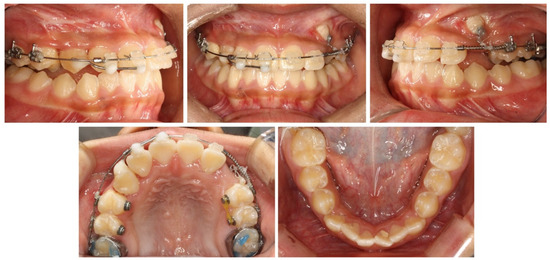

2.5. Treatment Results